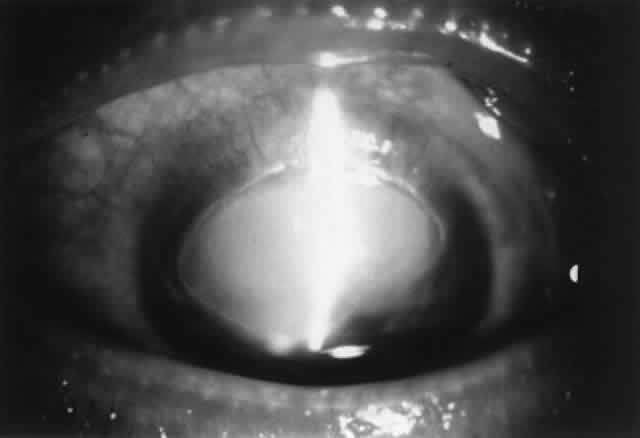

Treatment includes removal of the offending agent (including discontinuing eye drops) or avoidance (use of protective wear such as goggles, worksuits). In the acute stage of periocular contact dermatitis, cool compresses and topical nonfluorinated corticosteroids (e.g., hydrocortisone, desonide) can be used. In some cases, especially if severe, unresponsive to therapy, or associated with cutaneous ulcerations, cultures should be performed to rule out secondary infectious eczematoid dermatitis (usually staphylococcal or streptococcal in origin). Chronic periocular dermatitis requires maintenance of skin hydration and topical corticosteroids. In some cases (either acutely severe or chronic and unresponsive cases), a course of oral prednisone may be indicated. Contact conjunctivitis/keratitis may be soothed by application of nonpreserved artificial tears. A short course of topical corticosteroids may speed recovery, but one always should consider the possibility of further sensitization by the vehicle or the steroid itself.

MICROBIOALLERGIC DISEASE

Catarrhal Infiltrates and Ulcers

Catarrhal infiltrates typically occur in association with chronic staphylococcal blepharoconjunctivitis and are located in the peripheral cornea, separated from the limbus by a lucid interval. They are most commonly found at the two, four, eight, and ten o'clock positions, where the lid margins cross the peripheral cornea. These infiltrates are gray-white in color, may be single or multiple, and spread circumferentially rather than centrally, sometimes making partial rings. Overlying superficial ulceration often develops. There may be associated conjunctival injection or mild anterior chamber reaction. Symptoms include irritation, tearing, pain, and photophobia. Catarrhal ulcers are more common in adults than in children (compare with phlyctenulosis).